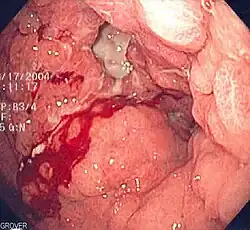

Krwawiący wrzód dwunastnicy

Choroba wrzodowa żołądka i dwunastnicy jest przyczyną około 50% przypadków krwawienia z górnego odcinka przewodu pokarmowego[19][20][21][22]. U około 15% chorych z chorobą wrzodową rozwija się krwawienie[46]. Choroba wrzodowa jest spowodowana przede wszystkim zakażeniem bakterią Helicobacter pylori, która odpowiada za 95% przypadków wrzodów dwunastnicy i 70% przypadków wrzodów żołądka[47][48]. Choć infekcję Helicobacter pylori w zależności od populacji obserwuje się u około 50–80% osób[49][50], to jednak choroba wrzodowa rozwija się u 6–20% zakażonych[49][48]. Szacuje się, że 20% chorych z obecnym wrzodem trawiennym doświadczy krwawienia z przewodu pokarmowego o różnym nasileniu w przebiegu choroby[51]. Jednak zaobserwowano, że częstość infekcji Helicobacter pylori jest niższa u chorych z krwawiącymi wrzodami niż u chorych z niekrwawiącymi wrzodami[52][49], możliwe więc, że infekcja Helicobacter pylori nie jest czynnikiem ryzyka wystąpienia krwawienia z wrzodu[51]. Z drugiej strony eradykacja zakażenia prowadzi do zmniejszenia ryzyka nawrotu krwawienia[53][54][55][56][57].

Jawne krwawienie z wrzodu jest skutkiem uszkodzenia naczyń krwionośnych przez kwaśną treść żołądkową, drążący w głąb ściany wrzód, choć faktycznie w przypadku każdego wrzodu dochodzi do przewlekłej utraty krwi[65][66]. Ryzyko krwawienia z wrzodu wzrasta u chorych przyjmujących niesteroidowe leki przeciwzapalne[67]. Bardzo rzadko stwierdza się krwawienie z wrzodu bez obecności zakażenia Helicobacter pylori lub stosowania niesteroidowych leków przeciwzapalnych[68]. Krwawienie ustępuje samoistnie w 80% przypadków[66]. Choroba wrzodowa objawia się głównie bólem w nadbrzuszu oraz niestrawnością, choć część chorych nie odczuwa żadnych objawów[20].